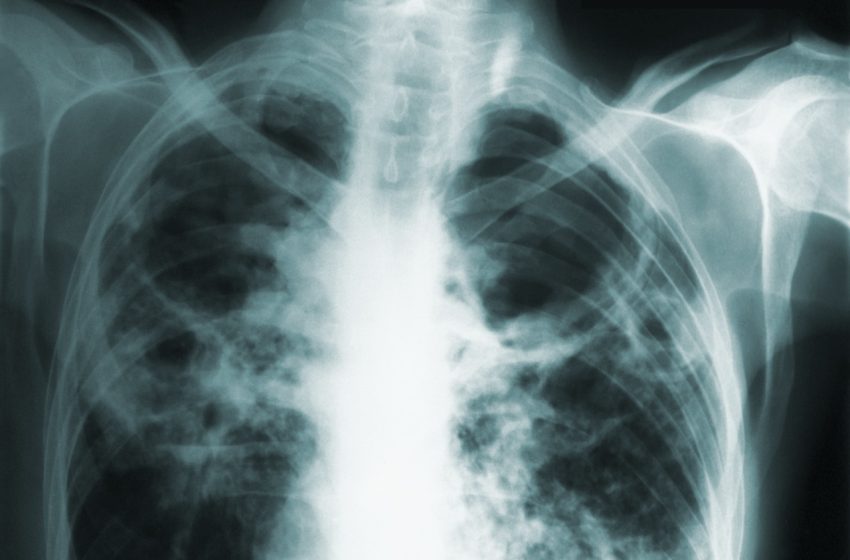

TB is a bacterium spread person-to-person through the air where it can remain for several hours. It’s often associated with coughing that lasts longer than two weeks, chest pain and coughing up blood, according to the Centers for Disease Control and Prevention.

While it usually attacks the lungs, it can attack other body parts such as the kidney, spine and brain.